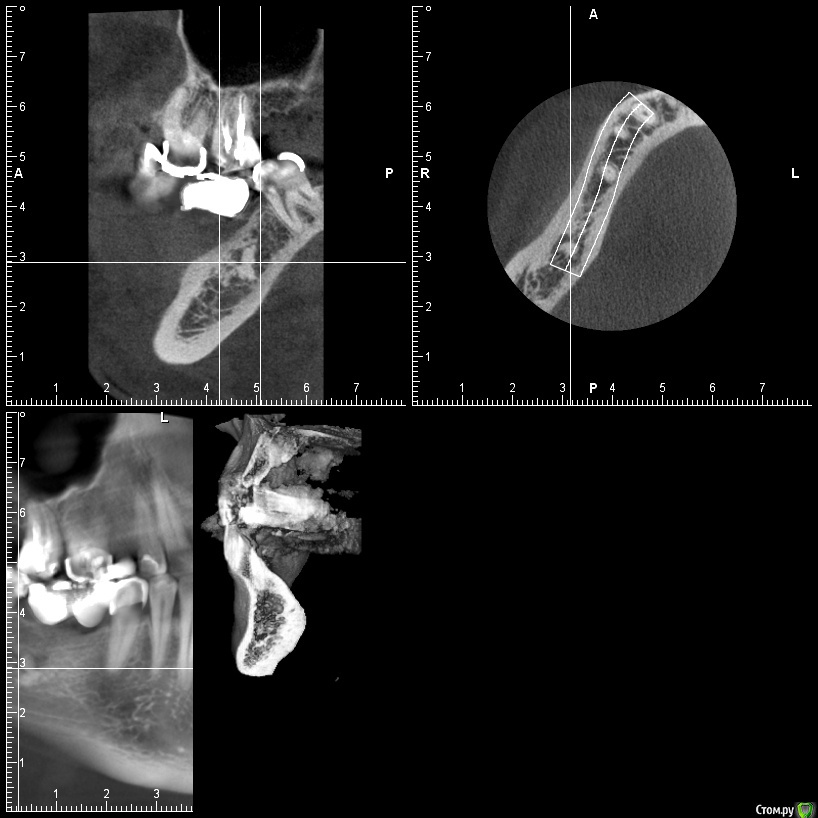

gum Опубликовано 7 июня, 2015 Поделиться Опубликовано 7 июня, 2015 Здравствуйте. Выкладываю снимок с остеомой. ставить имплантат в нее или есть варианты. спрашивал уже на форуме, не было КТ. Ссылка на комментарий